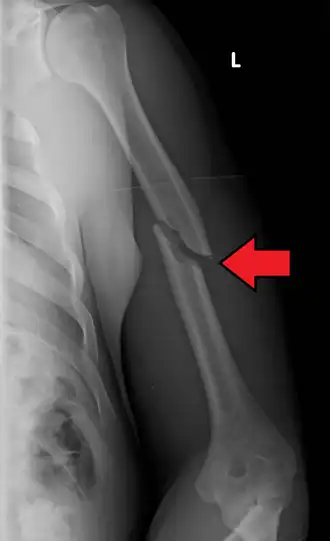

Fratura de úmero se refere a ruptura do úmero, o maior osso do braço. As fraturas proximais são próximas ao ombro (25% dos casos), mediais na diáfise (60% dos casos) e as distais ocorrem próximo ao cotovelo (15% dos casos). Essa classificação pode ser subdividida, com base na extensão da fratura e nas partes específicas do úmero. [1]

Quando há suspeita clínica são solicitadas duas radiografias, frente e perfil ou duas oblíquas, dependendo do local afetado. Tomografia computadorizada pode dar mais informações sobre a fratura.[8]